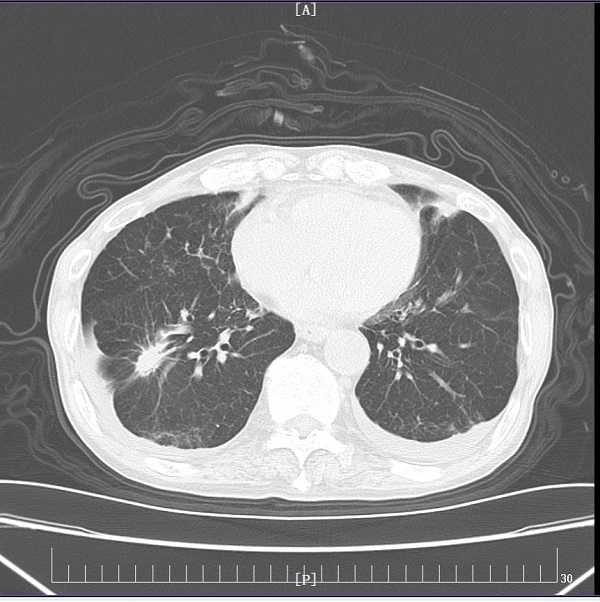

充分研究病情后,刘娟妮主任团队积极与家属沟通,对症治疗的同时,在CT引导下行经皮肺穿刺活检术,术后病理提示:中分化腺癌,基因检测结果提示:EGFR Exon19突变。明确诊断后,刘娟妮主任团队一边安慰患者及家属的情绪,一边对患者的全身状况及疾病进行了充分的评估,邀请相关科室会诊,经MDT讨论并结合患者目前症状、基因检测结果分析及国内外最新指南推荐,制定了个性化的治疗方案,给予口服三代靶向药控制肿瘤。治疗1个月后,复查头颅MRI及胸部CT,结果显示患者肺原发肿瘤、脑多发转移瘤较前均缩小、部分消失。

治疗前

治疗后